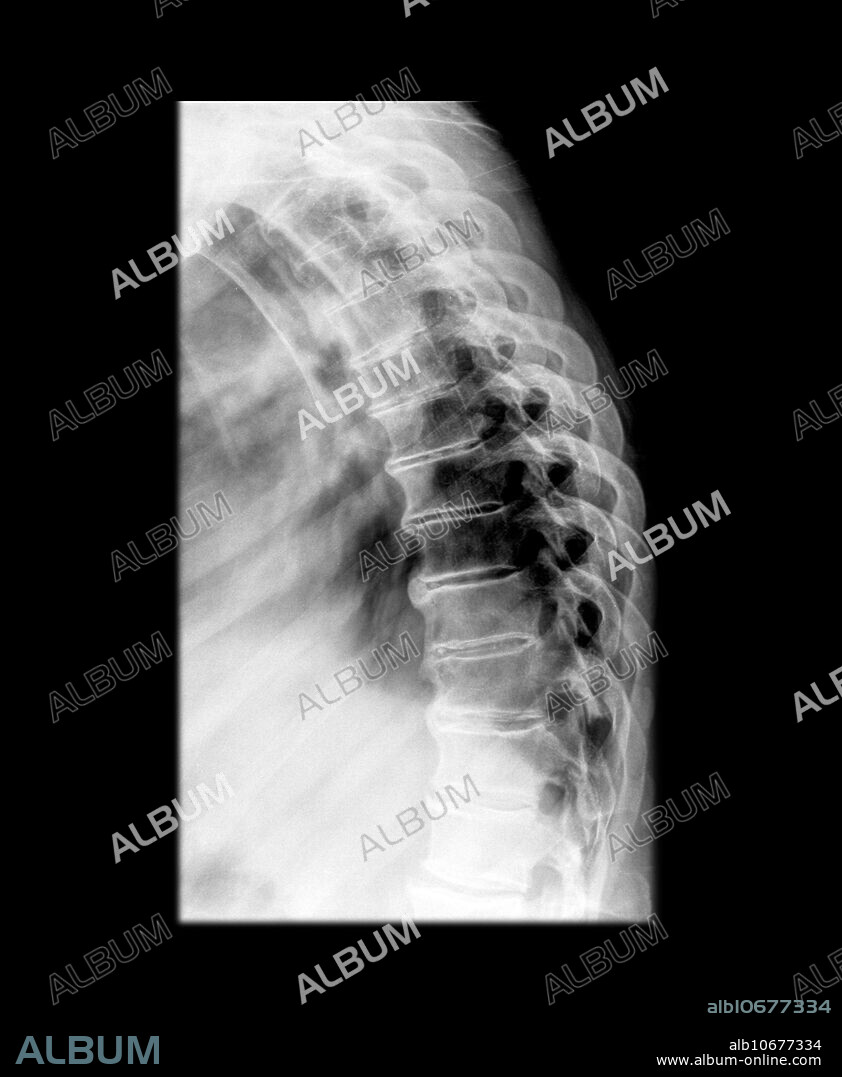

Degenerative Disc Disease

This lateral x-ray of the thoracic spine demonstrates multilevel degenerative changes with disc space narrowing and multilevel vertebral margin osteophytes. Osteoporosis is noted.

Titre: Degenerative Disc Disease